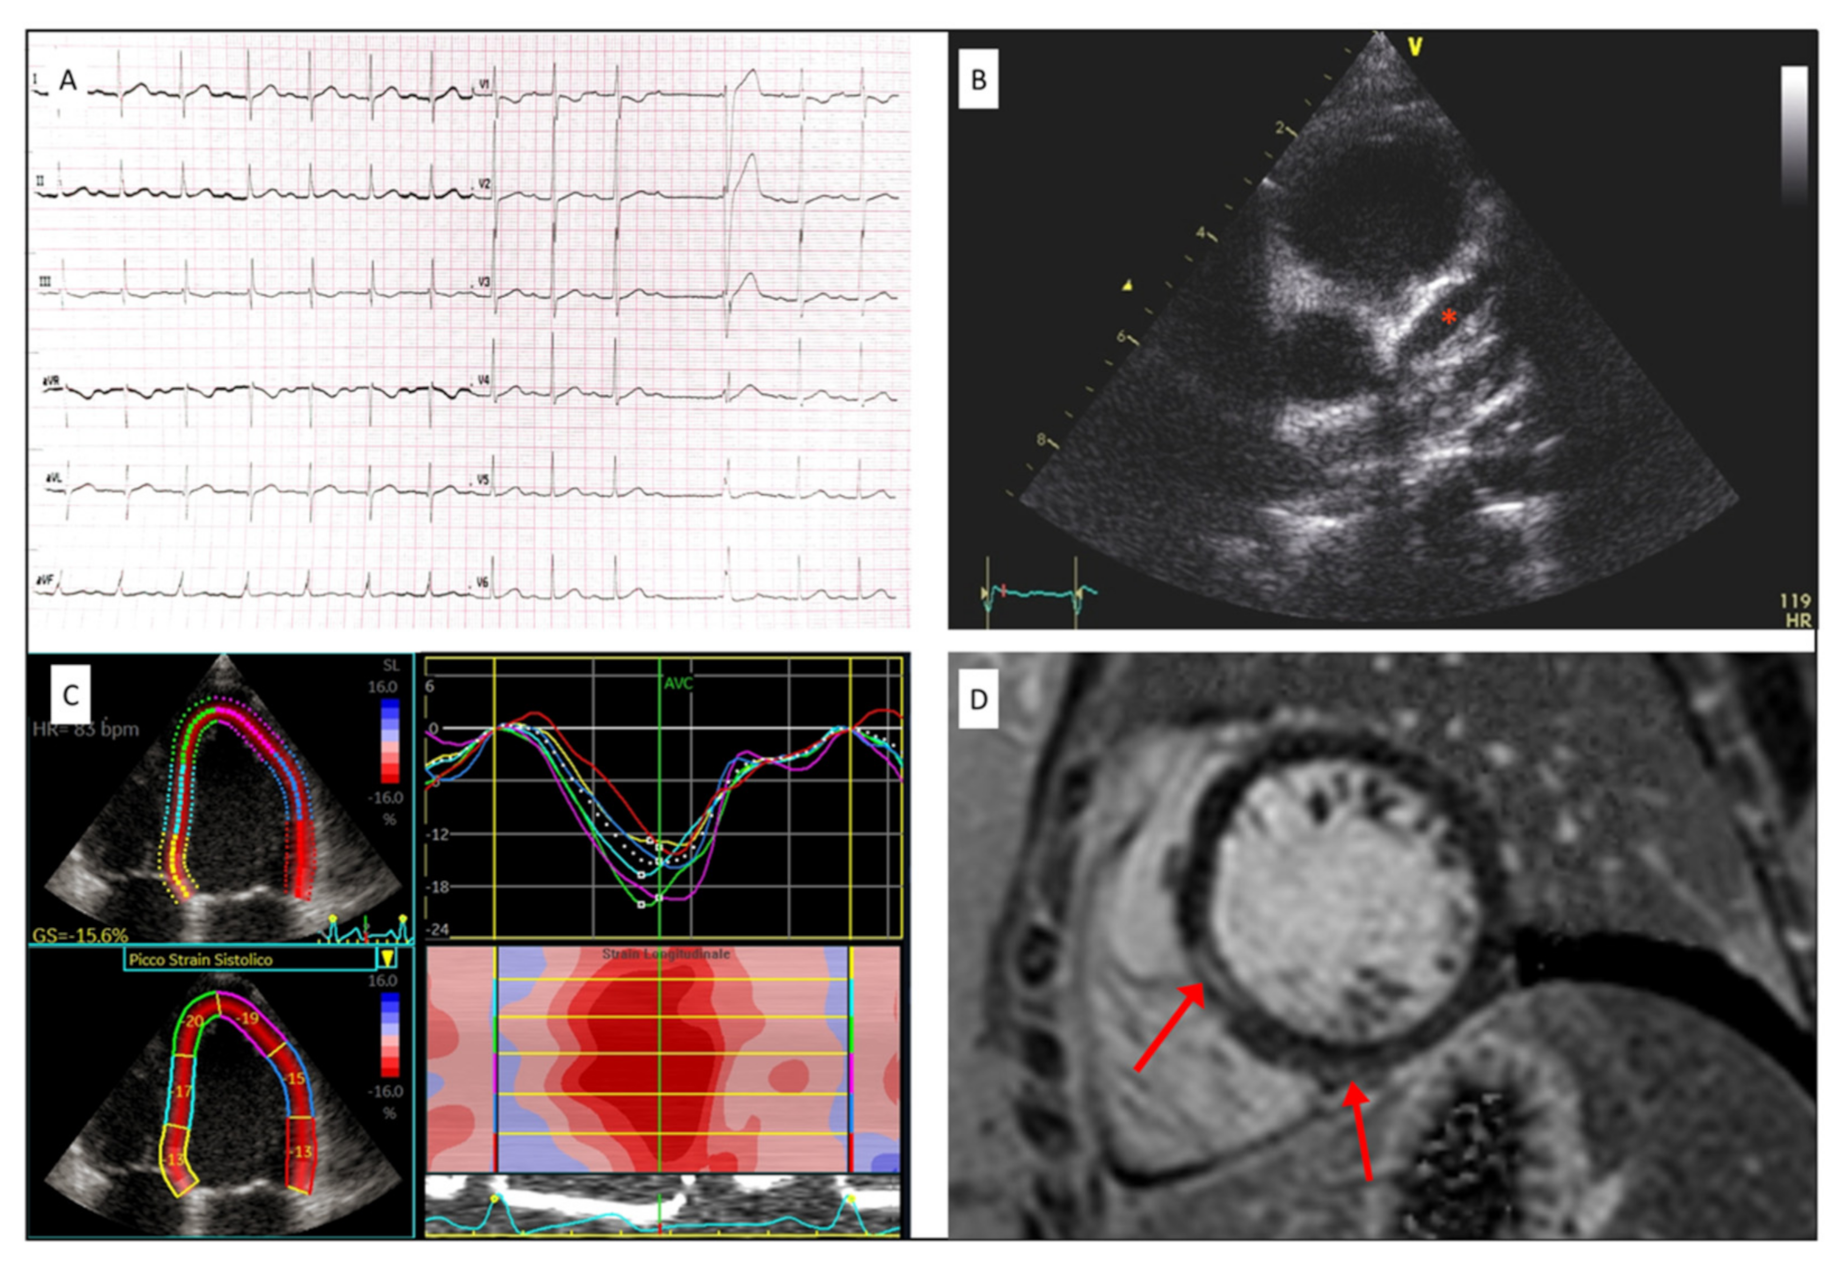

C misura dello strain longitudinale in 4 2 e 3 camere nei 17 segmenti in cui ĆØ suddiviso il ventricolo sinistro con bulls eye del picco di strain sistolico longitudinale segmentale. Descriviamo lesame della funzione cardiaca fetale con lecocardiografia fetale funzionale contemporanea e feto-placentare. The follow-up was possible for 72 of them.

Jcm Free Full Text Early Echocardiographic And Cardiac Mri Findings In Multisystem Inflammatory Syndrome In Children Html

Jcm Free Full Text Early Echocardiographic And Cardiac Mri Findings In Multisystem Inflammatory Syndrome In Children